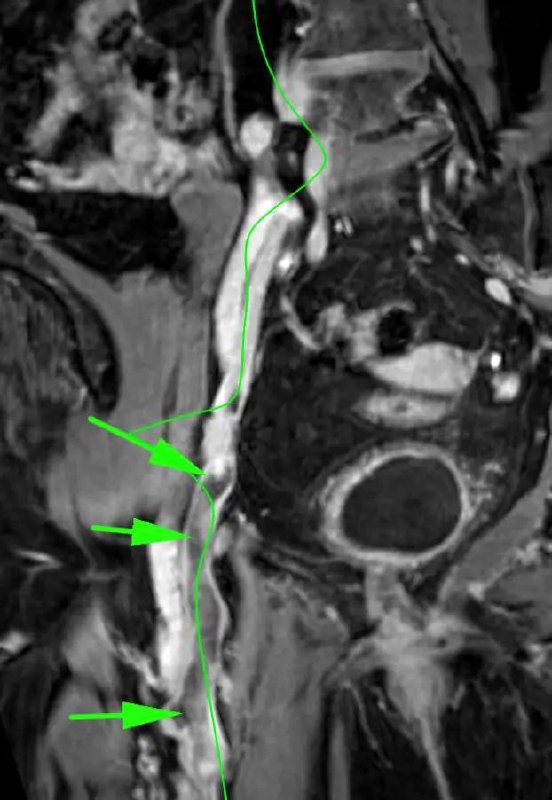

Парень 14 лет. Около 2 недель назад - травма при игре в футбол.

Отслойка хряща - это отделение суставного хряща в месте прикрепления от подлежащей субхондральной кости, считается хирургической патологией с риском значительного нарушения функции, если оно не распознано и не лечено должным образом.

Для аргументации в пользу верности собственного мнения приводится картинка из свободно доступной публикации.